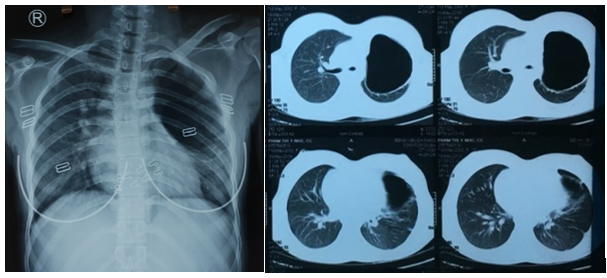

Figure 1. Chest x-ray and CT scan showing a giant bulla of the left upper lobe with compression of the remaining lung parenchyma.

A 17-year-old woman was admitted to the Thoracic Surgery Department of Da Nang Hospital in Vietnam with left chest pain, cough, and dyspnea. The medical history of this patient revealed a persistent cough for several months when she was 10 years old. Physical examination demonstrated decreased breath sounds in the left thorax. There were no other abnormal clinical findings. A routine chest x-ray and computed tomography confirmed the presence of a giant bulla of the left upper lobe (Figure 1).